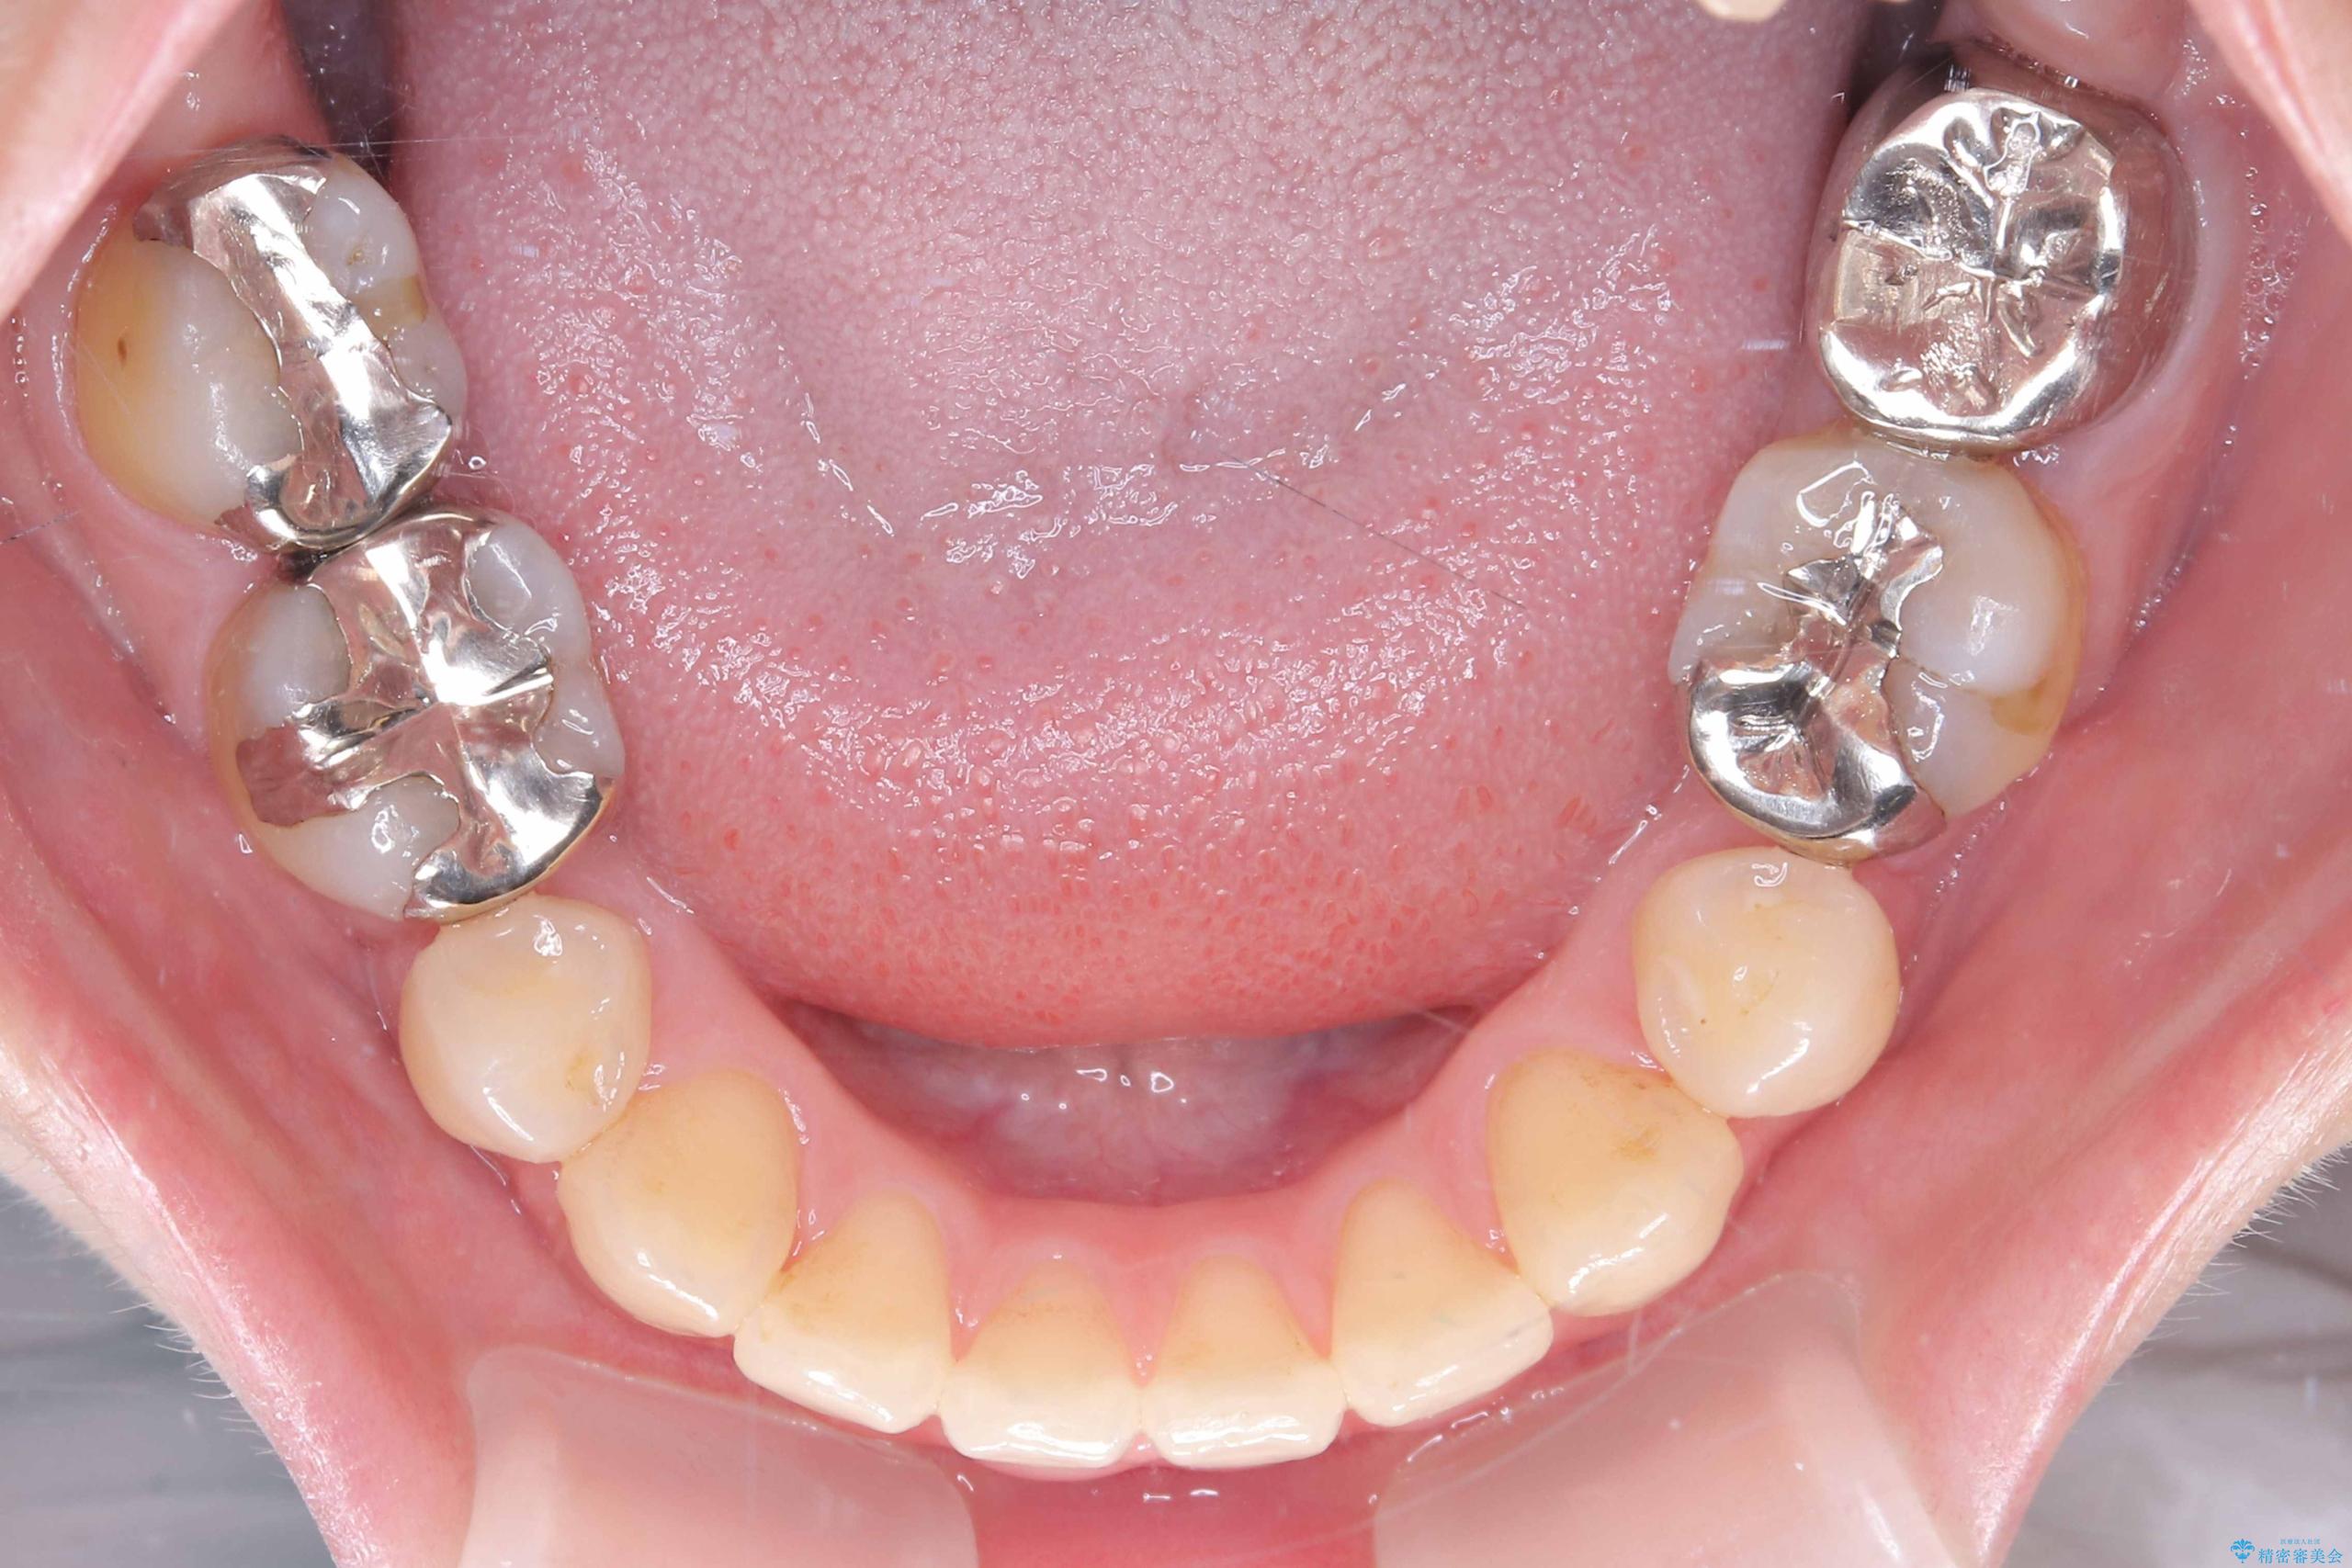

- 開咬と歯のデコボコ(叢生)、八重歯を主訴にご来院された患者様です。

矯正の精密検査の結果、上顎左右4番および下顎左右5番の計4本を抜歯し、ワイヤー矯正(クリア装置)にて治療を行いました。

虫歯があったので、虫歯治療は矯正前に行っています。